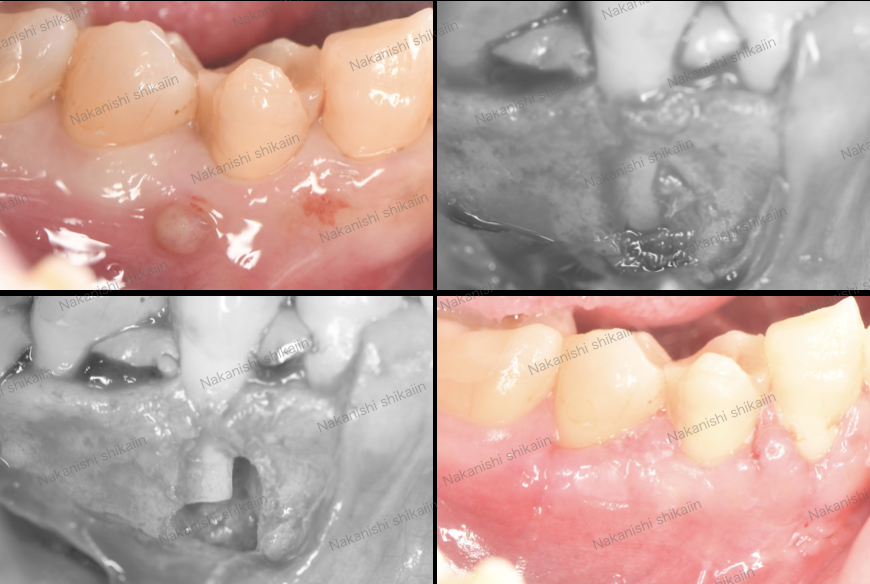

歯根端切除の実際です。写真のように、歯茎がぷくっと腫れていて、治っていない状態が確認できます。

麻酔をした上で、歯茎を切開し、内側を目視します。根の先に出来モノを確認しました。あとはこれを綺麗に取り除くだけです。

縫合し、約1週間程度で抜糸します。

このように、外科的な治療で最終的には治癒に至ります。

次も似たような状態ですが、写真のように根の治療でも、歯茎が腫れて治っていない状態です。

歯茎を捲ると、根の先と悪い部分が確認できます。これを綺麗に取り除きます。

1週間後の写真です。腫れていた歯肉が治っているのがわかります。